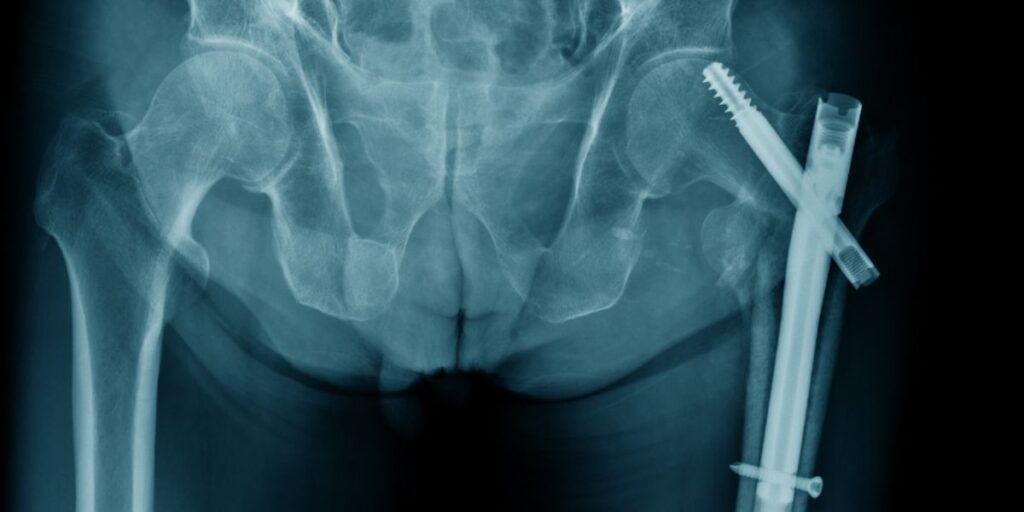

Η διάγνωση ενός κατάγματος ισχίου γίνεται κυρίως μέσω απλών ακτινογραφιών λεκάνης και ισχίων. Σε ορισμένες περιπτώσεις, όταν η ακτινογραφία δεν δείχνει ξεκάθαρα το κάταγμα αλλά υπάρχει ισχυρή κλινική υποψία, μπορεί να χρειαστεί περαιτέρω έλεγχος με αξονική ή μαγνητική τομογραφία.

Β. Διατροχαντήριο / Υποτροχαντήριο Κάταγμα

• Αυτά τα κατάγματα απαιτούν σχεδόν πάντα χειρουργική επέμβαση.

• Η πιο συχνή χειρουργική τεχνική είναι η τοποθέτηση ειδικού ενδομυελικού ήλου (Gamma Nail), που επιτρέπει σταθεροποίηση του κατάγματος με ελάχιστα επεμβατικό τρόπο.